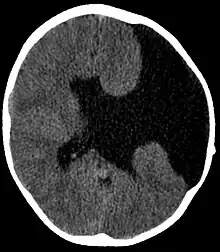

A esquizencefalia é uma rara malformação congênita que se caracteriza por fenda unilateral ou bilateral nos hemisférios cerebrais. Essa fenda normalmente se estende do córtex à região periventricular.

Pode pertencer ao tipo I, quando as duas corticais são justapostas (denominada esquizencefalia de lábios fechados) ou ao tipo II, quando a fenda é preenchida por líquido cefalorraquidiano (denominada esquizencefalia de lábios abertos).[1]

A tomografia computadorizada é capaz de detectar a anomalia, embora a ressonância magnética seja mais recomendada por proporcionar análise mais detalhada.[2]